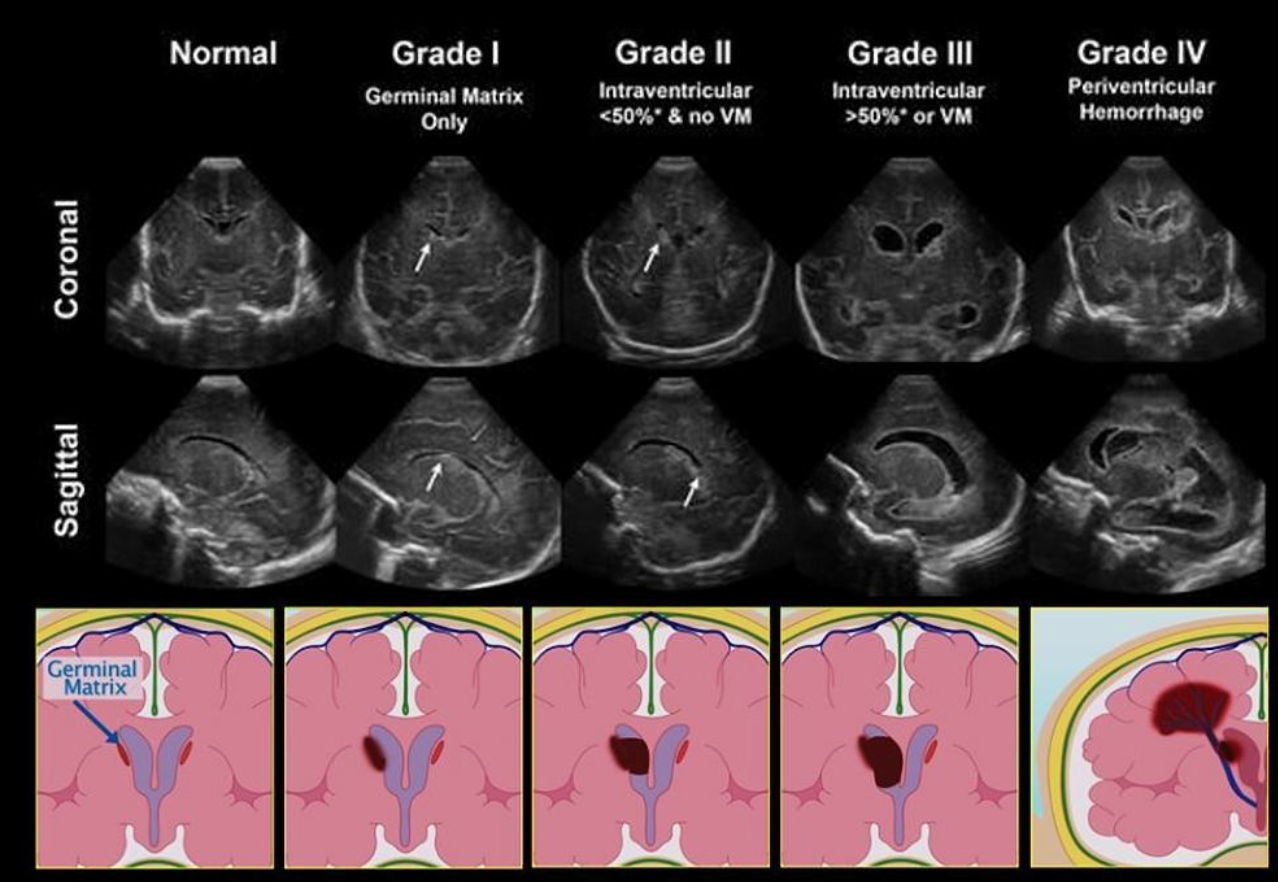

Germinal Matrix Hemorrhage

• The choroid plexus should not extend past the caudothalamic groove

• If you see bright stuff near there then suspect it is blood

• Only seen until 32-34W gestation

• You cannot have germinal matrix hemorrhage in a full term infant

• There is normally some increased echogenicity in the periventricular white matter

• So how do we know what is blood vs normal brain

• If prominently asymmetric = likely blood

• If area of increased echogenicity is as echogenic or more echogenic as the choroid plexus = likely blood

• Normal peri-ventricular brain should be echogenic but not more than the choroid plexus

• Can you identify borders of the echogenic area

• If yes = likely blood

• Normal brain will be more vague

• Relevance of Grading

• If grade 1 = can continue anti-coagulation (kids classically on AC for ECMO)

• If grade 2 or higher = typically need to stop AC and therefore stop ECMO

• Grading

• Grade 1: Sub-ependymal hemorrhage

• Can progress to grade 2

• Can resolve or sometimes form a subependymal cyst